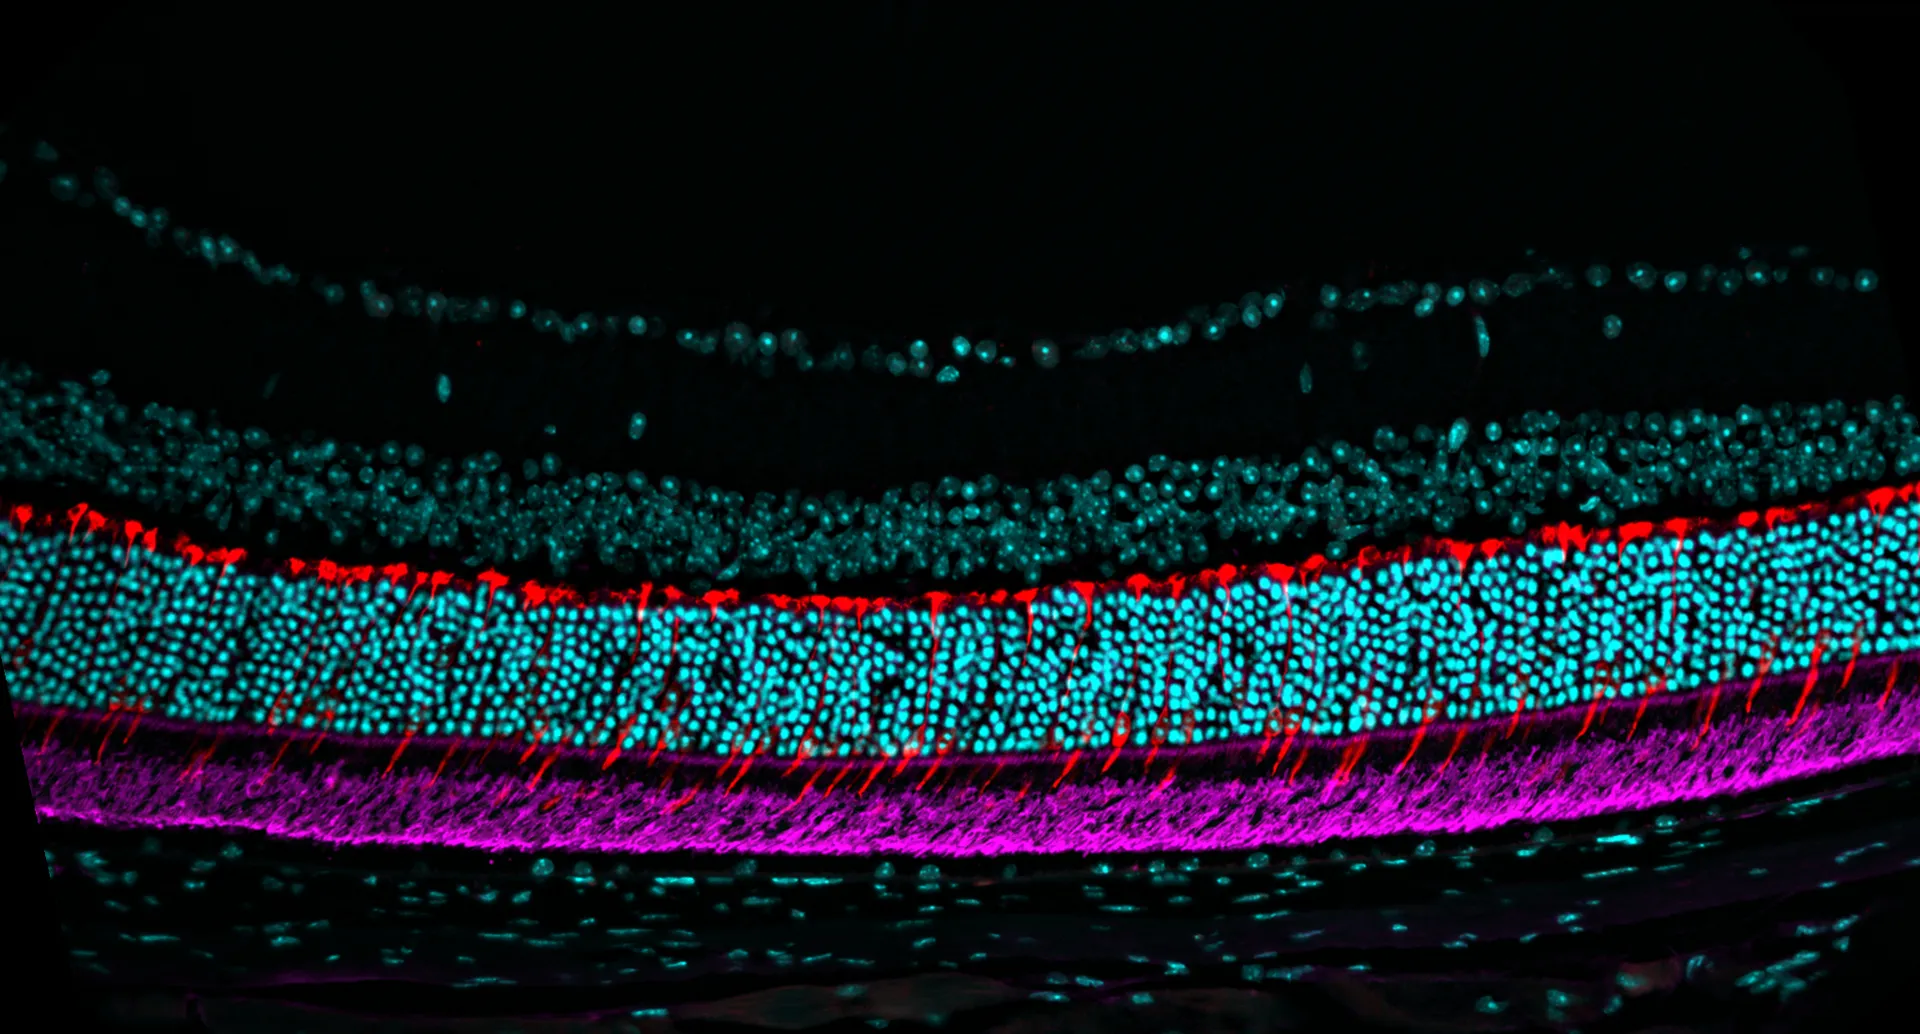

At Experimentica we offer studies with Pde6brd1 and RhoP23H (B6.129S6(Cg)-Rhotm1.1Kpal/J) mouse models. Pde6brd1 mice homozygous for the rd1 mutation show an early onset of severe retinal degeneration due to a murine viral insert and a second nonsense mutation in exon 7 of the Pde6b gene (Bowes et al.). P23H mice (The Jackson Laboratory Strain #:017628) carry the P23H mutation in the rod opsin gene (proline to histidine at codon 23), one of the most common causes of autosomal dominant retinitis pigmentosa (adRP). Heterozygous mice mimic the progressive retinal degeneration seen in patients, with early shortening of rod outer segments and photoreceptor loss by postnatal day 63. Homozygous mice display a more severe phenotype, including rapid degeneration and near-complete loss of photoreceptors by day 63 (Sakami et al.).

Retinal morphology is monitored utilizing spectral-domain optical coherence tomography (SD-OCT), while visual function is evaluated using flash electroretinography (fERG) and optomotor response (OMR). These non-invasive techniques enable comprehensive monitoring of disease progression with longer follow-up periods. Additionally, we provide histology and immunohistochemical stainings, enabling detailed analysis of tissue morphology and molecular markers to assess disease progression and treatment efficacy.

– Immunohistochemistry (IHC)